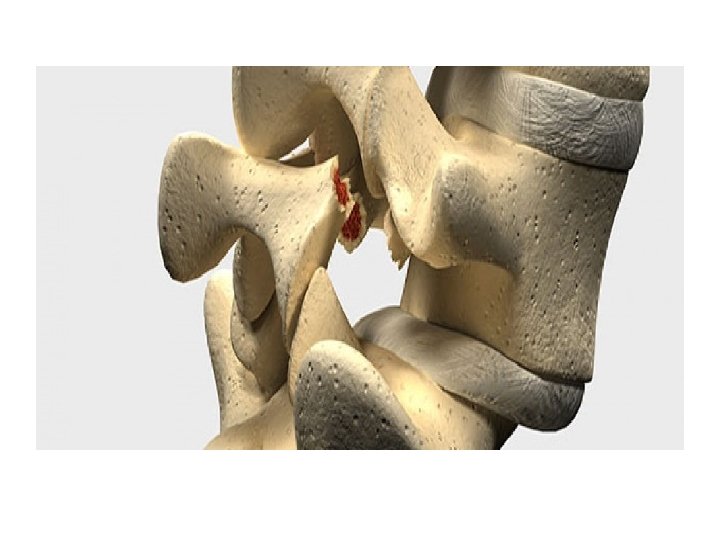

• Pathophysiology : Compression can lead to either foraminal stenosis mainly , lateral recess stenosis or rarely central stenosis. § foraminal stenosis : mainly : – Adult isthmic spondylolisthesis at L 5/S 1 often leads to radicular symptoms caused by compression of the exiting L 5 nerve root in the L 5 -S 1 foramen. compression can be caused by : • hypertrophic fibrous repair tissue of the pars defect • uncinate spur formation of the posterior L 5 body • bulging of the L 5/S 1 disc § lateral recess stenosis • caused by facet arthrosis mainly or hypertrophic ligamentum flavum. § central stenosis • rare due to fact that these slips are usually only Grade I or II

• Isthmic : 50 % - Typically presents in the teenage or early adulthood years even the presentation may be in the late middle age. - Location : mostly (82 %) at L 5/S 1 and may be L 4/L 5. - Etiology : defect in pars interarticularis – on both sides( acquired by microtrauma or congenital ) or elongation of P. I due to repetitive breaking and healing. • The condition is more common than usual in those whose spines are subjected to extraordinary stresses (e. g. competitive gymnasts and weight-lifters). • Genetic factors may play a role.